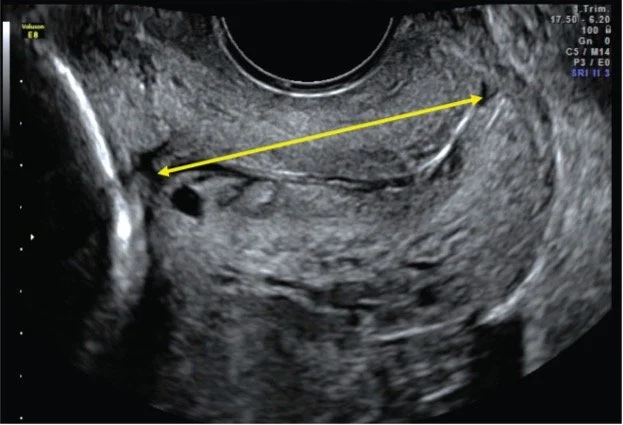

Join us at the Library of Birmingham for a public screening of The Only One, a newly commissioned video and sound work by composer Hannah Conway, now acquired by the Birth Rites Collection. Created in close collaboration with women undergoing cervical scans, writer Hazel Gould and Professor Anna David, the work draws on 16 hours of research and interviews at the Elizabeth Garrett Anderson Wing, University College Hospital London. Co-commissioned by Tommy's Preterm Birth Research, Imperial College London and the Birth Rites Collection, the work also forms part of a training resource for midwives.